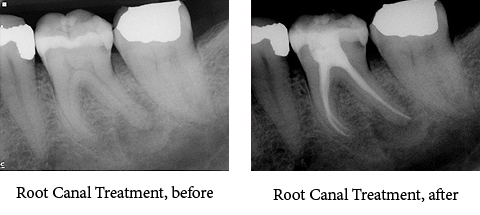

• Root Canals

Orthodontic Treatment X-ray - After